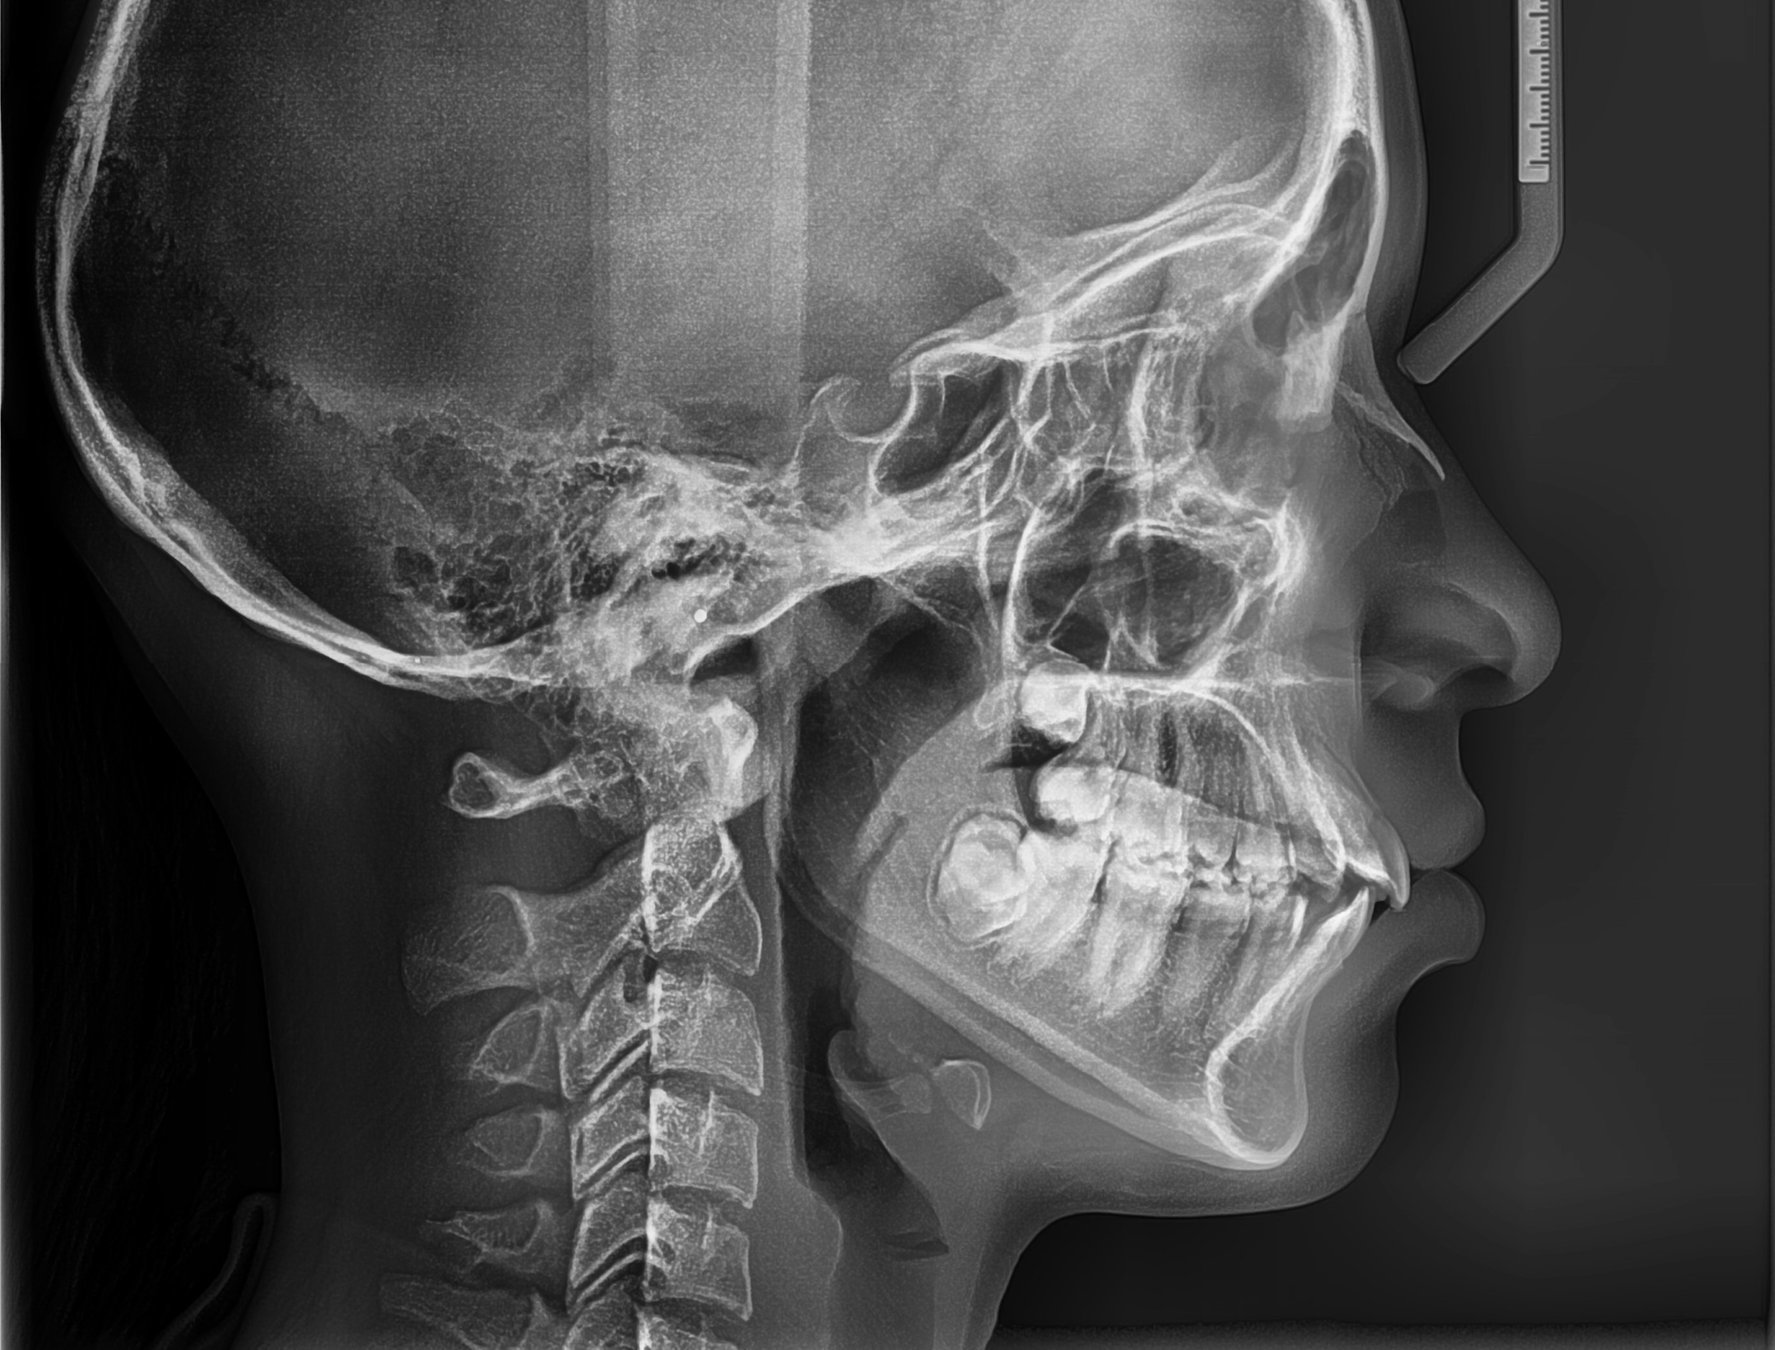

Телерентгенография в стоматологии: как работает аппарат